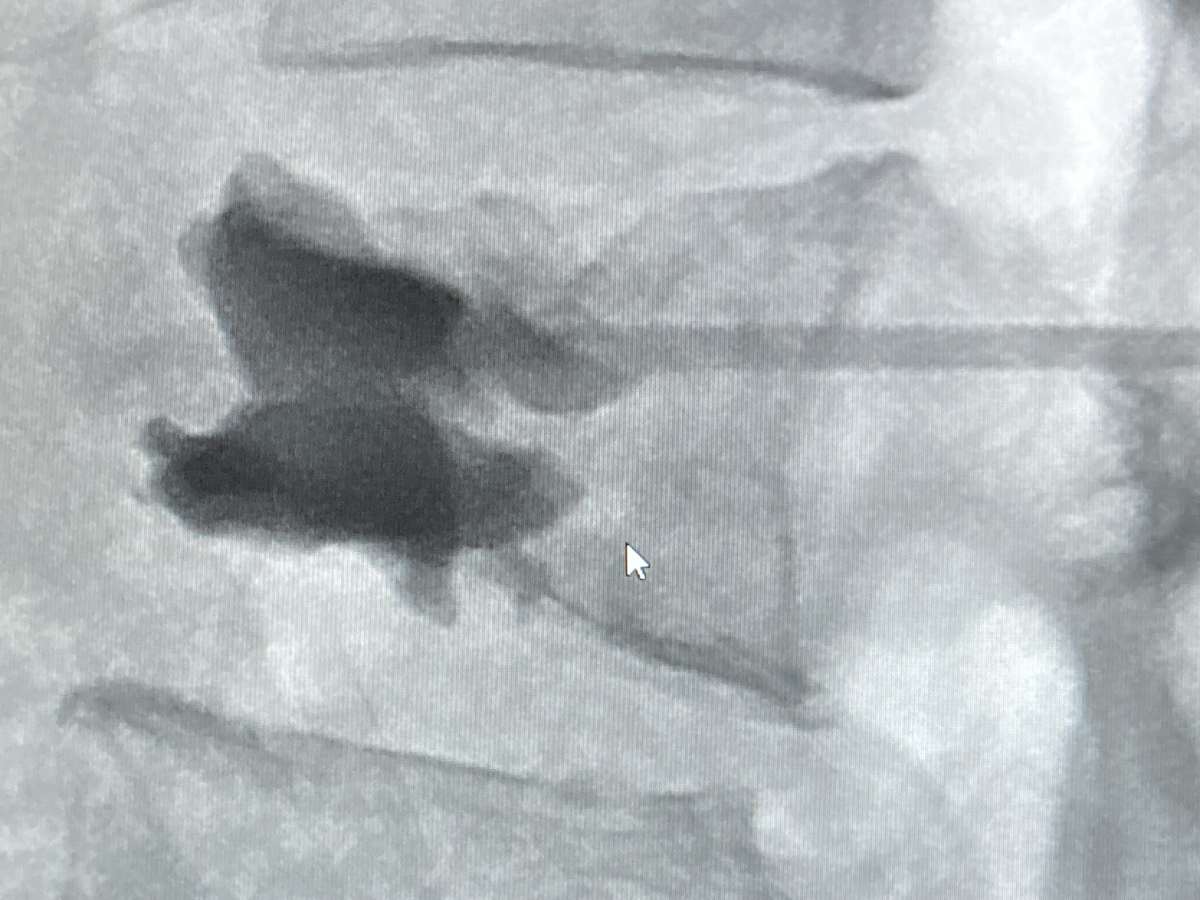

The main goal of the trip was to teach the technique of vertebroplasty as treatment for painful spine compression fractures. We treated 3 patients, all of whom became pain free, after suffering from months of severe pain. The Interventional Radiology team was enthusiastic learning a new technique, and has since treated 5 more patients after I left, under the guidance of another proctor, all of whom had pain relief. We are looking at setting up an audiovisual link so that the Tanzania team can watch me do cases and continue to learn with the goal of having the Tanzania team become fully independent providing this care. It may also be possible to create a formal teaching relationship between my hospital in the US and another major Tanzanian hospital in the capital city of Dodoma.